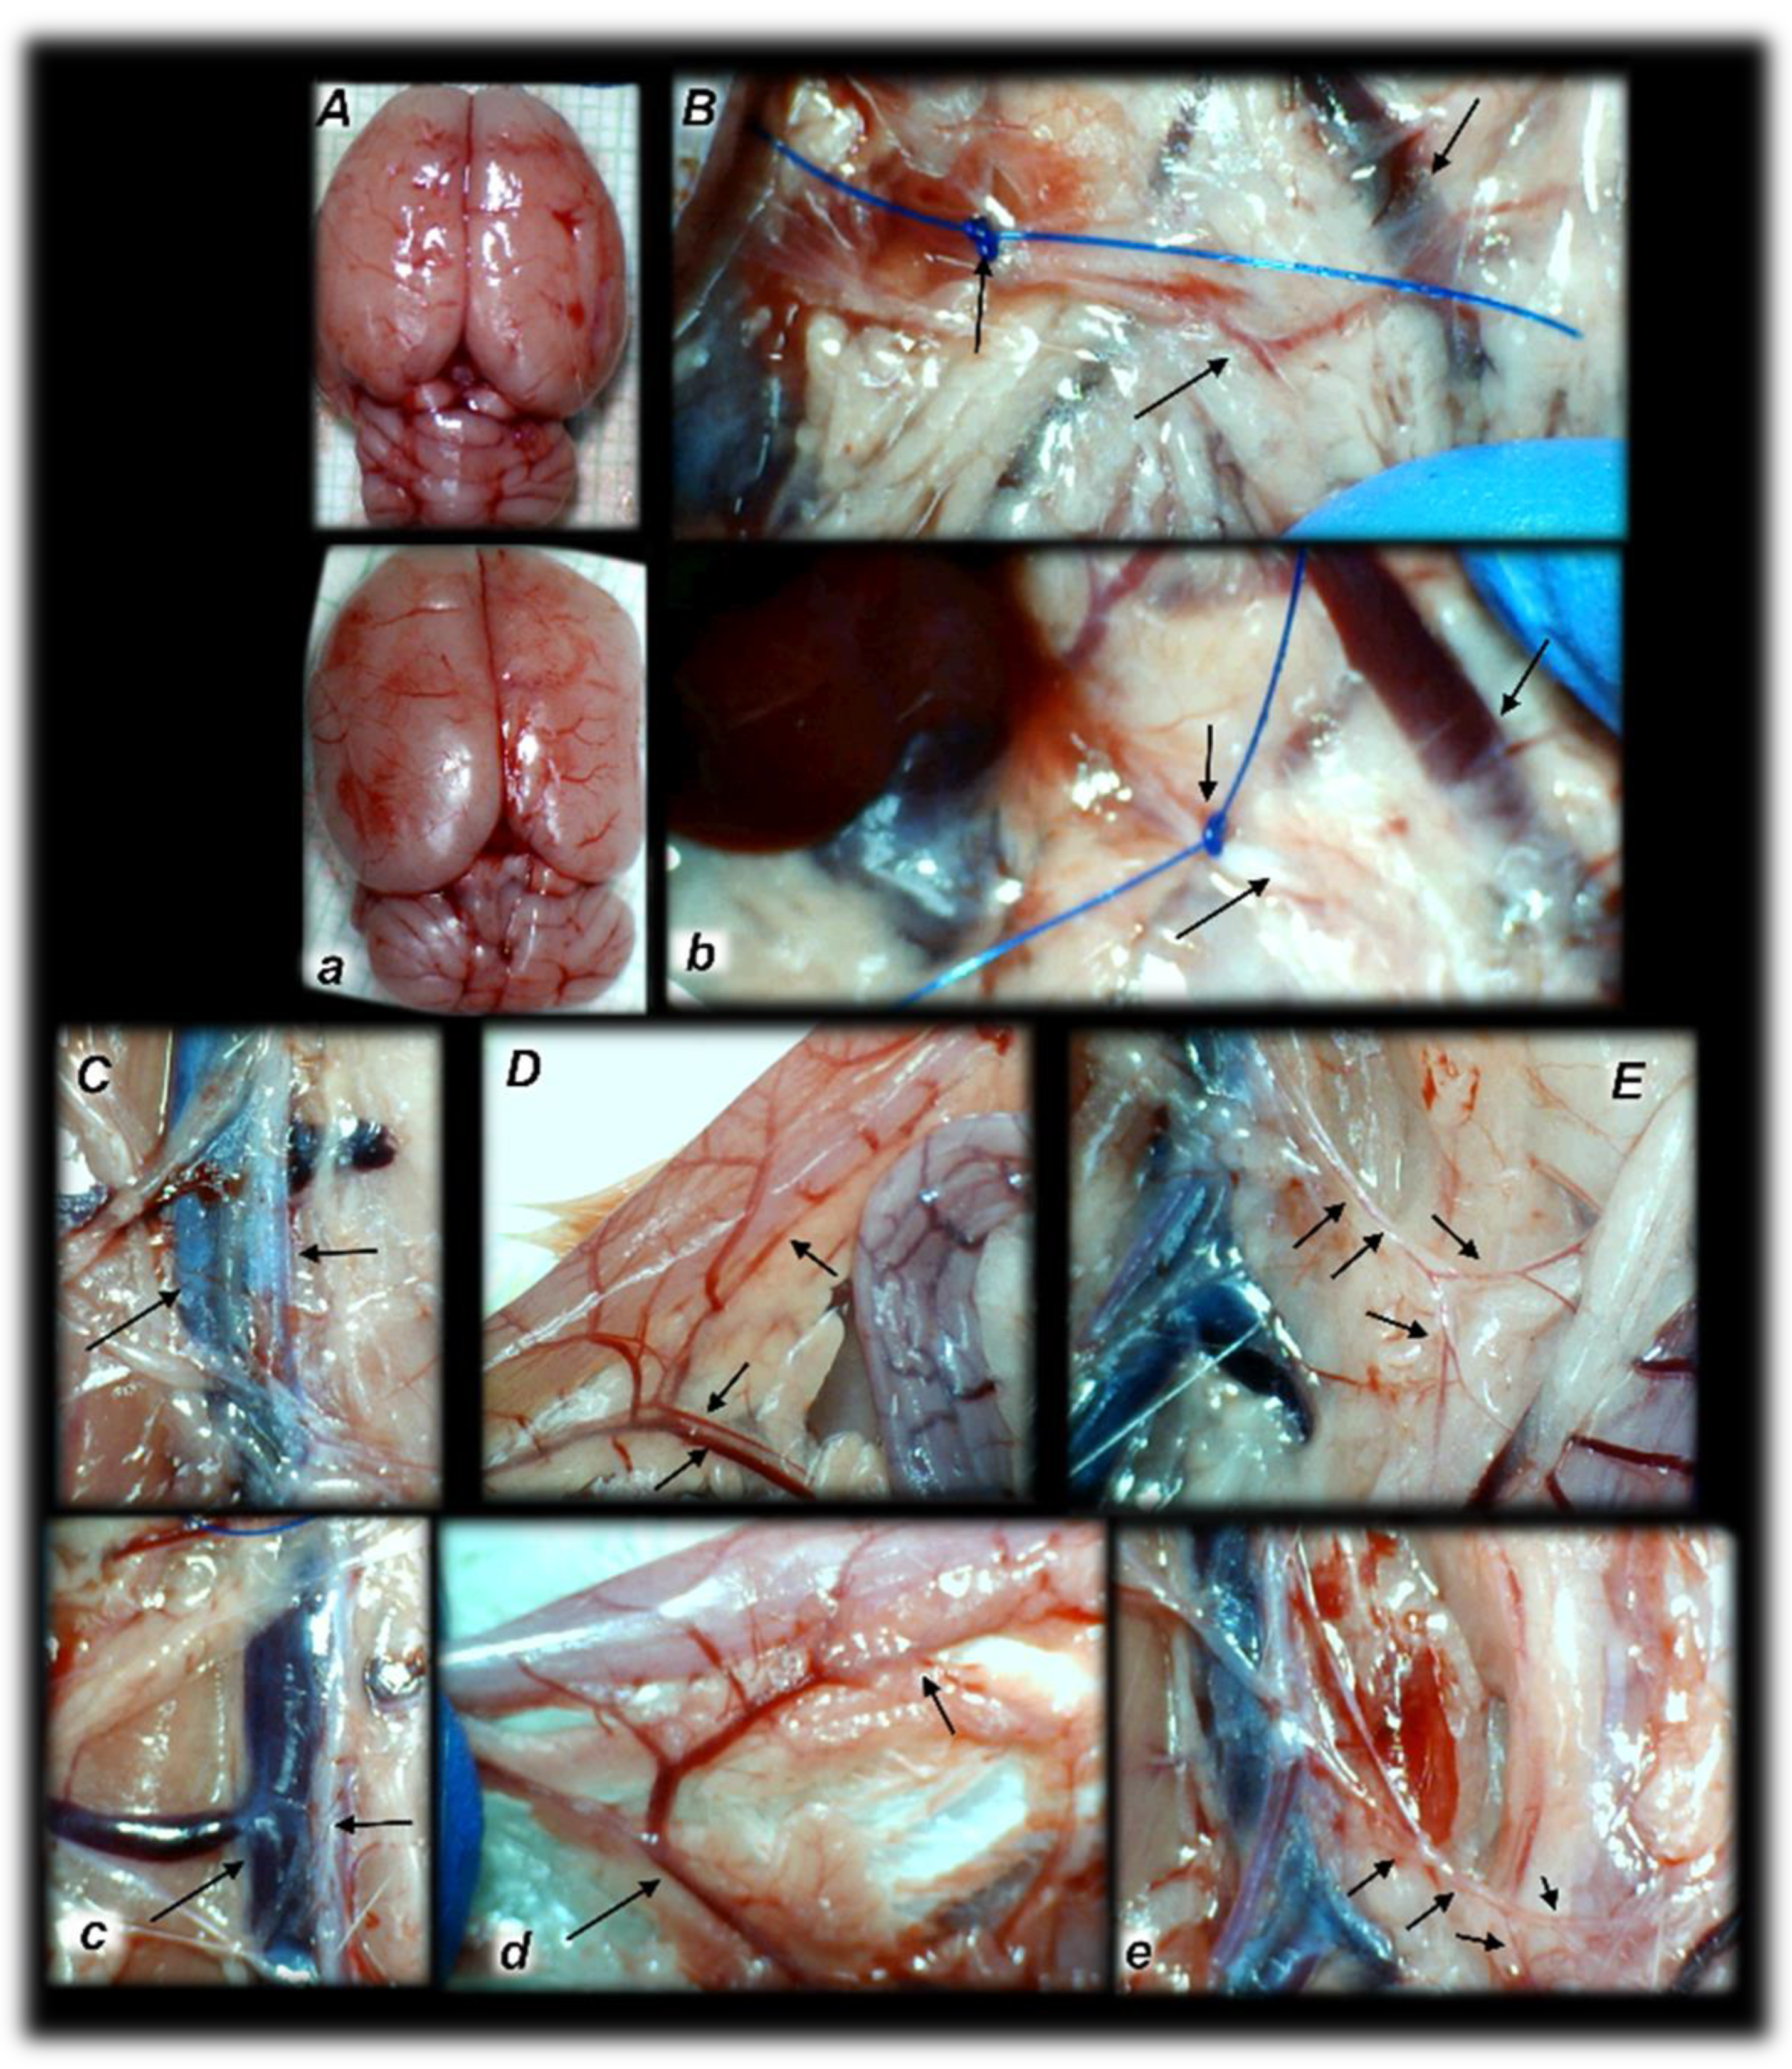

Figure 14. Brain histology. Control rats presented increased edema and congestion and an increased number of karyopyknotic cells in the cerebral (a) (HE, ×200) and cerebellar cortex (b) (HE, ×400). Contrarily, BPC 157-treated rats exhibited a few karyopyknotic neuronal cells in the cerebral (A) (HE, ×200) and cerebellar cortex (B) (HE, ×400).

Figure 15. Brain histology: Control rats presented increased edema and congestion and an increased number of karyopyknotic cells in the hippocampus cortex (a) and hypothalamus (b), (HE, ×200). Contrarily, BPC 157-treated rats exhibited a few karyopyknotic neuronal cells in the hippocampus cortex (A) and hypothalamus (B) (HE, ×200).

Commonly, unless therapy was given, rats with an occluded superior mesenteric artery exhibited an increased number of karyopyknotic cells in all four region: cerebral and cerebellar cortex, hypothalamus, thalamus, hippocampus cortex, and hypothalamus/thalamus (Figure 14 and Figure 15). Neuropathologic changes in cerebral cortex areas revealed increased edema and congestion. Especially, karyopyknosis and degeneration of Purkinje cells of the cerebellar cortex and marked karyopyknosis of pyramidal cells of the hippocampus were observed. Contrarily, BPC 157 rats showed a few karyopyknotic neuronal cells in the analyzed neuroanatomic structures.